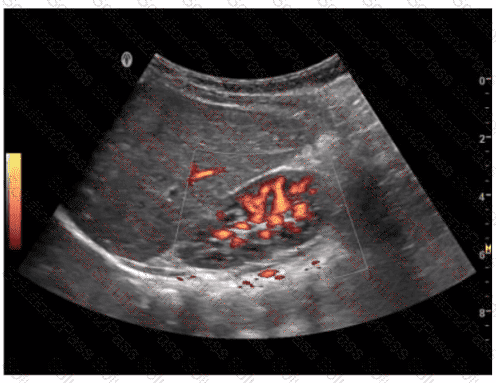

What does this image demonstrate?

A.

Presence of flow

B.

Direction of flow

C.

Color aliasing

D.

Color inversion